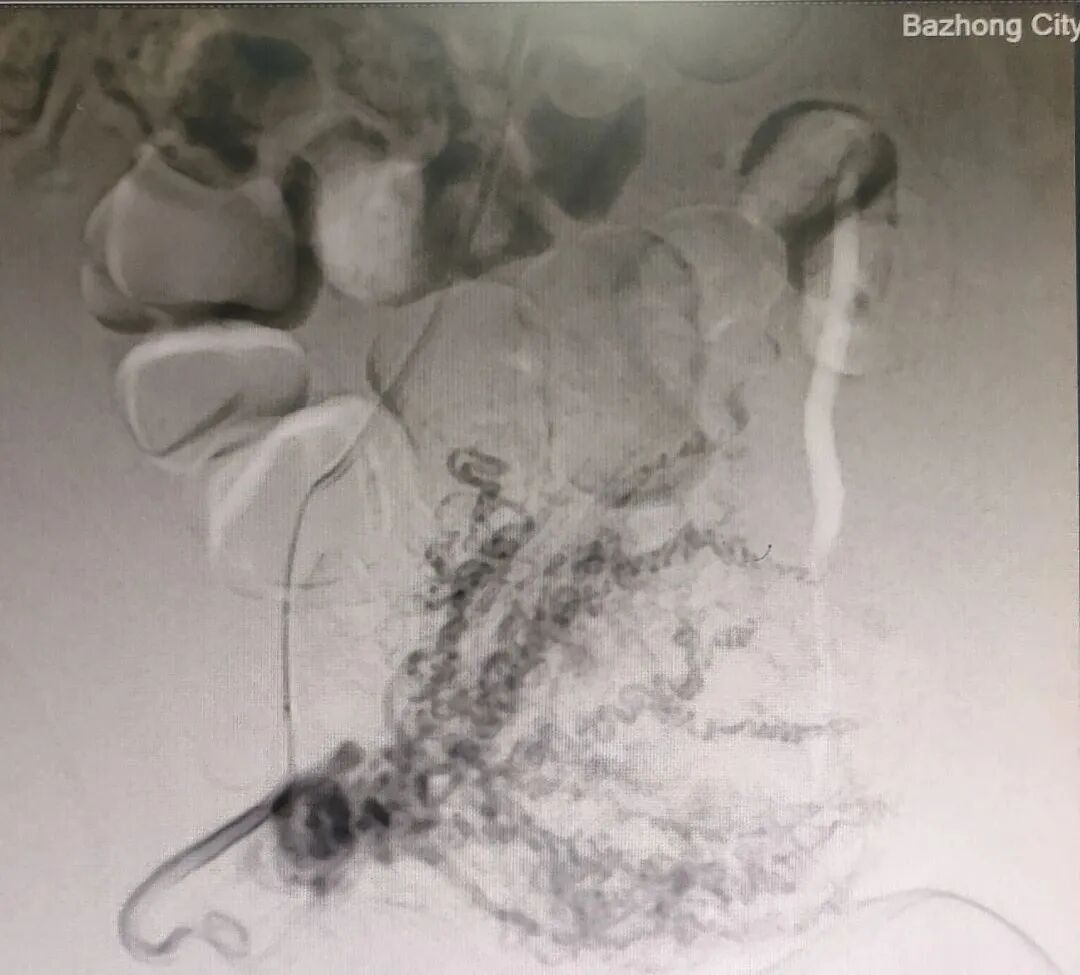

术后影像

图片   图片